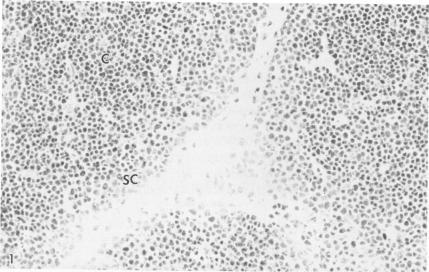

The pattern of expression of cell surface antigens and their relationship to the sequence of T-cell differentiation were delineated by the application of a series of monoclonal antibodies against T cells on tissue sections. The morphologic features and location of T-cell differentiation can be categorized into four stages: 1) subcapsular thymocytes, 2) cortical thymocytes, 3) medullary thymocytes, and 4) peripheral T cells. Phenotypically, on the basis of reactivity with monoclonal antibodies, T cells could be separated into two groups: immature and mature T cells. All stages of T cells expressed T200, Lyt 3, Leu 1, OKT3, Leu 9, and TA1, although staining intensities varied between thymic cortex and medulla. Mature T cells (medullary thymocytes and peripheral T cells) stained more intensely than immature T cells for some antigens, such as Leu 1, OKT3, and Leu 9, and, therefore, probably have a greater antigen density. Immature T cells, exemplified by subcapsular and cortical thymocytes, were characterized by the expression of Tdt, Leu M3, OKT6, OKT9, J5, BA-2, OKT10, and usually coexpressed both helper (T4/Leu 3a) and suppressor (T8/Leu 2a) antigens. With further maturation, medullary thymocytes and peripheral T cells lost reactivity for the above-mentioned markers, acquired A1G3 and Leu 8, and segregated into either T4+/Leu 3a+ or T8+/Leu 2a+ cells. A subpopulation of T cells in germinal centers differs from the majority of peripheral T cells by virtue of an absence of expression of Leu 8/A1G3. This histologically localized subset of T cells may be responsible for the mediation of helper function within the germinal center.